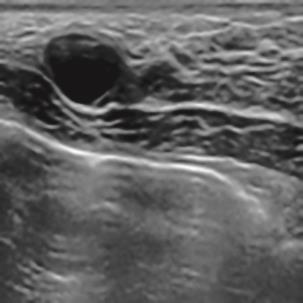

基于逐通道空间自适应选择核卷积与双向边界感知机制的乳腺超声图像病变分割网络

A Breast Ultrasound Images Lesion Segmentation Network Based on Channel-Wise Spatially Adaptive Selective Kernel Convolution and Bidirectional Boundary-Aware Mechanism

乳腺癌是全球女性最常见的恶性肿瘤之一,准确的病变分割对于乳腺癌的早期诊断与治疗具有重要意义。然而,由于病变形态的多样性以及超声成像机制的复杂性,现有基于深度学习的乳腺超声图像病变分割方法在分割准确性方面仍面临巨大挑战。为进一步提升乳腺超声图像中病变区域的分割精度,该文基于经典U-Net架构,提出了一种新型乳腺超声图像病变分割网络(CWSASKM-BBAM-Net)。首先,在网络中引入逐通道空间自适应选择核卷积模块(CWSASKM),根据不同通道的语义特征为每个空间位置自适应选择感受野大小,以增强多尺度信息的建模能力;然后,引入双向边界感知机制(BBAM),通过融合正向与反向注意力,对目标显著区域及其边界进行协同建模,同时逐步提升对非显著区域与病变区域的区分能力,以进一步强化边界信息的表达;最后,在3组公开乳腺超声图像数据集(BUSI、UDIAT和STU)上开展分割实验。结果表明:该方法在数据集BUSI上的杰卡德指数、精确率、召回率和Dice相似系数分别为71.97%、82.85%、81.40%和80.44%,较次优方法分别提升1.69、1.05、1.28和1.84个百分点;在数据集UDIAT上,这4项指标分别达到78.14%、88.31%、86.73%和86.10%,较次优方法分别提升了2.75、2.04、0.56和2.01个百分点;在外部数据集STU上,该方法也取得了优于其他方法的整体表现。实验结果表明,CWSASKM-BBAM-Net在乳腺超声图像分割任务中展现出更优的整体性能。